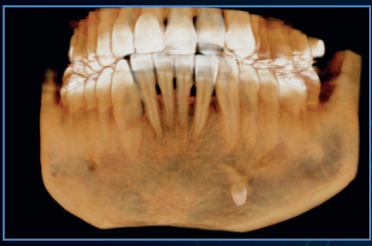

Metal Artifact Reduction (MAR)

The PreXion Excelsior ENDO line features three processing levels that can be chosen to correct gutta-percha deformities, implants and/or full arch prosthesis and metal restorations, in addition to automatic metal reduction. This tool also allows image reprocessing, for a better diagnosis, preventing the need to generate new exposure to the patient.